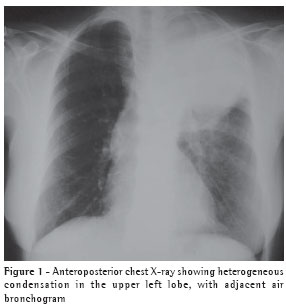

The computed tomography scan of the chest (Figure 2) confirmed the presence of a heterogeneous mass in the left upper lobe, with air bronchogram adjacent to the mass, suggesting an expansive neoplastic lesion. The patient was unable to produce a sputum sample for testing.

There is no characteristic radiological profile, although the presence of single or multiple nodules that are well defined and not calcified is more common and can mimic neoplasia on the X-ray.(5,9) Radiographic alterations have been reported, including infiltrates (62%), nodules (38%), masses (19%), cavitations (14%) and pleural effusion (3%), without anatomical distribution patterns and without any accompanying hilar or mediastinal lymph node enlargement. Empyema, pneumothorax and pleural involvement suggestive of Pancoast tumor,(13) as well as lung masses invading the chest wall,(14) have also been reported in the literature. A computed tomography scan of the chest corroborates the radiological findings, providing better details for the differential diagnosis,(11) and, when necessary, helps program the invasive diagnostic techniques. In the present case, the patient presented a lung mass that mimicked neoplasia.